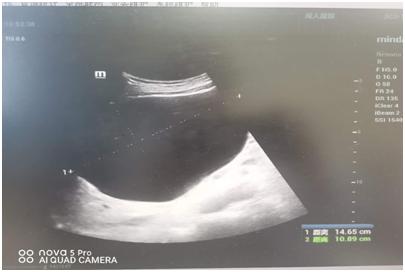

近来患者疼痛加剧,来到王府医院就诊,超声检查提示:患者肝脏多发囊肿,肝脏左叶可见一巨大囊肿,几乎未见正常肝组织,大小约14.7x10.9cm。经专家会诊,患者需马上进行治疗。

朱双利主任详细地为患者介绍了超声引导下肝囊肿穿刺硬化治疗的方法,及其与传统外科手术的区别。经患者同意,朱双利主任带领其团队在超声引导下定位进行穿刺、抽吸囊液,共抽吸液体950ml,抽吸后,巨大囊肿消失,使用硬化剂无水乙醇完成硬化治疗。治疗后仅可见“针尖样”治疗创口,术后患者腹部不适症状立刻缓解,观察30分钟无不良反应,自行安返回家。